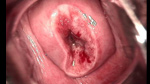

• 宮頸息肉宮頸息肉

• 宮頸息肉 leep術后宮頸息肉 leep術后

• 宮頸息肉 leep術一周后宮頸息肉 leep術一周后

• 宮頸息肉 leep術兩周后宮頸息肉 leep術兩周后

• 宮頸息肉 leep術三周后宮頸息肉 leep術三周后

• 宮頸息肉 leep術50天后宮頸息肉 leep術50天后